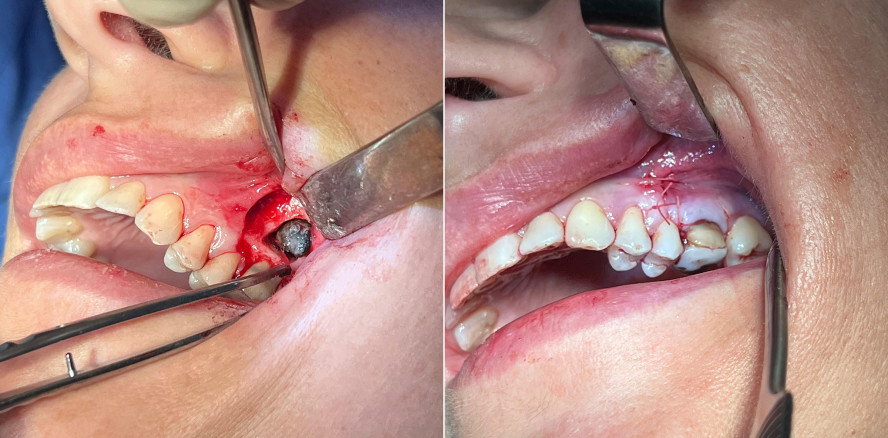

Nach ausführlicher Aufklärung wurde gemeinsam mit der Pa­tien­tin entschieden, den Zahn 26 durch eine Wurzelspitzen­resektion (WSR) zu erhalten und gleichzeitig den Fremd­­körper über den WSR-Zugang aus der Kieferhöhle in Lokal­­anäs­­thesie zu entfernen. Die operative Maßnahme erfolgte unter antibiotischer Abschirmung mit Amoxicillin/Clavulansäure.

Intraoperativ wurde ausgeprägtes entzündliches Weich­gewebe in der linken Kieferhöhle sichtbar, das vollständig entfernt wurde. Zudem konnte ein schwarz-grünlicher, bröcke­liger Fremdkörper geborgen werden, der makroskopisch dem Erscheinungsbild eines Fungusballs entsprach. Die histopathologische Untersuchung bestätigte den Verdacht: Es fanden sich multiple Myzelstrukturen, vereinbar mit einem Myze­tom (Fungusball).

Bereits unmittelbar postoperativ berichtete die Patientin über eine deutliche Besserung der nasalen Atmung und ein subjektives Freiheitsgefühl im linken Mittelgesicht. Bei der postoperativen Kontrolle wurde eine regelrechte Wund­heilung mit lediglich zeitgemäßem Wundschmerz beob­achtet, jedoch ohne erneutes Druckgefühl oder Schwellung.